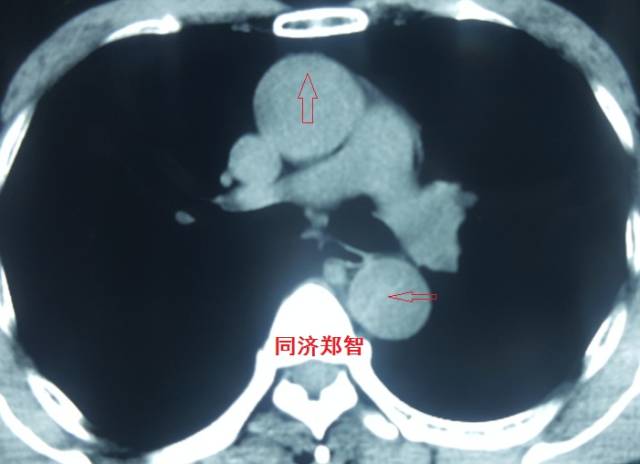

平扫CT提示升主动脉及降主动脉内膜片,CTA证实为A型主动脉壁间血肿。

图14-15